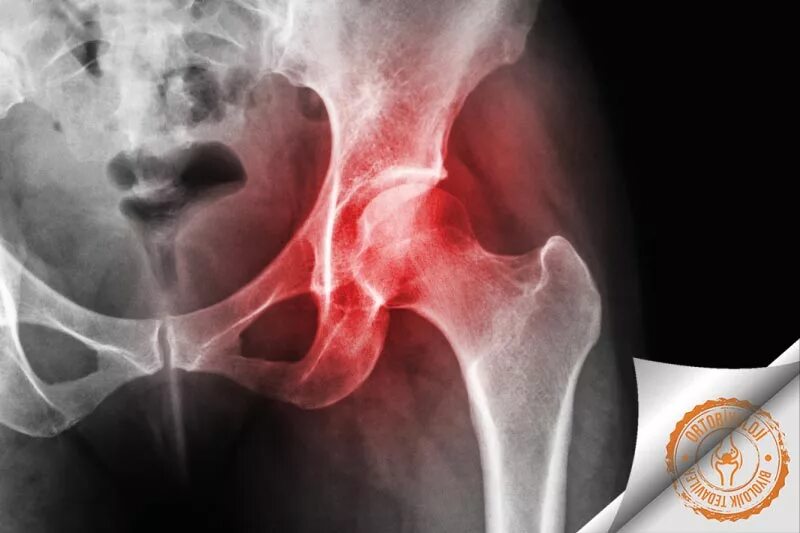

Некроз суставов лечение